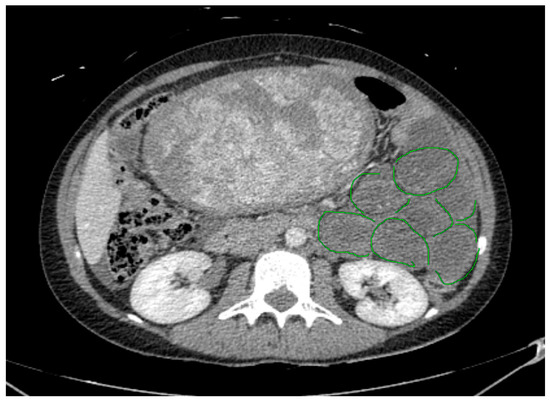

Background: Meckel’s diverticulum on the mesenteric side has been reported only as case reports in the literature and presents a diagnostic challenge, with ultimate recognition often taking place intraoperatively. We describe a case series of children with mesenteric Meckel’s diverticulum (MMD) treated at [...] Read more.

Background: Meckel’s diverticulum on the mesenteric side has been reported only as case reports in the literature and presents a diagnostic challenge, with ultimate recognition often taking place intraoperatively. We describe a case series of children with mesenteric Meckel’s diverticulum (MMD) treated at our institution, along with the results of a systematic review of the literature. Methods: Our experience on MMD was analyzed along with a systematic literature review performed according to PRISMA criteria. We identified studies published from 1941 to 2023 from PubMed, EMBASE, SCOPUS, and WOS. Search terms were variations of “Meckel”, “diverticulum”, and “mesenteric”. Inclusion criteria were patients < 18 years of age and articles written in English. Results: A total of three cases of MMD were observed and treated in our hospital. The mean age was 7.6 years. The most common symptoms were rectal bleeding and abdominal pain. Diagnostic workup included ultrasound and both upper and lower endoscopy. Surgery was performed by the laparoscopy-assisted technique. One case had to be reoperated due to postoperative intestinal occlusion. The mean length of hospital stay was 9.3 days. The literature search yielded 795 citations; out of the 590 papers remaining after the exclusion of 205 duplications, only 15 papers matched the inclusion criteria and were included and analyzed. Conclusions: MMD remains a rare and elusive pathology, sharing with its normal counterpart symptoms and signs. In our experience, and in the more recent literature, laparoscopy-assisted surgery appears safe and effective both for final diagnosis and definitive treatment. Full article